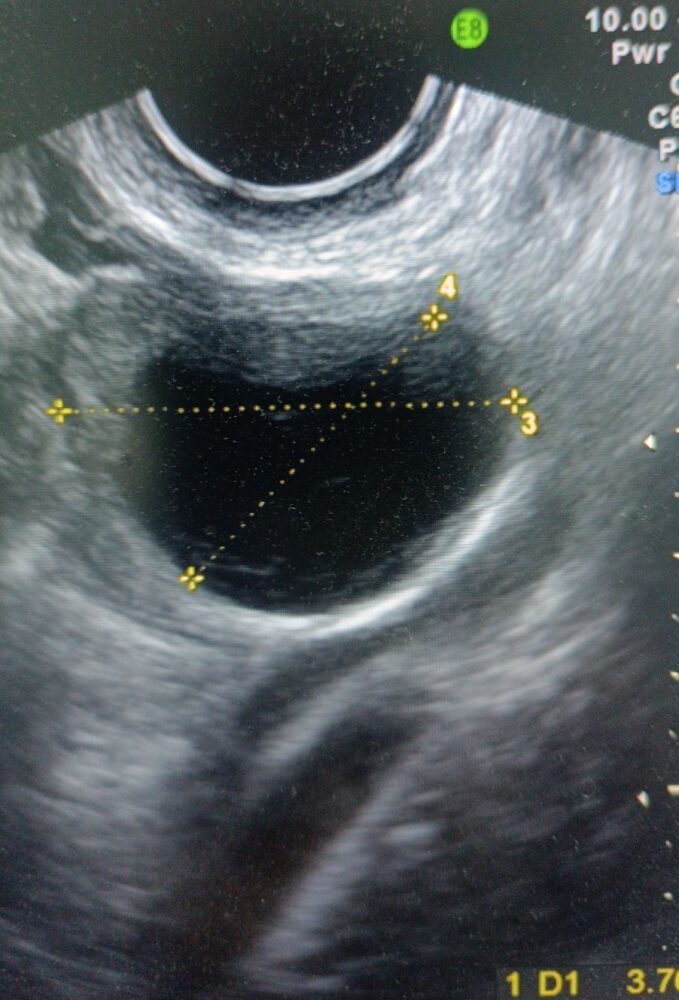

Це утворення видно під час ультразвукового обстеження. Кіста жовтого тіла на УЗД, фото якої можна побачити на цій сторінці, має вигляд округлого утворення, однокамерного, з гладкими стінками. Вміст часто буває неоднорідним через вкраплення крові. Навколо кісти жовтого тіла за допомогою режиму доплерографії можна побачити так зване “вогняне кільце”, тому що кровоплин у цій області інтенсивний, це характерна ознака.